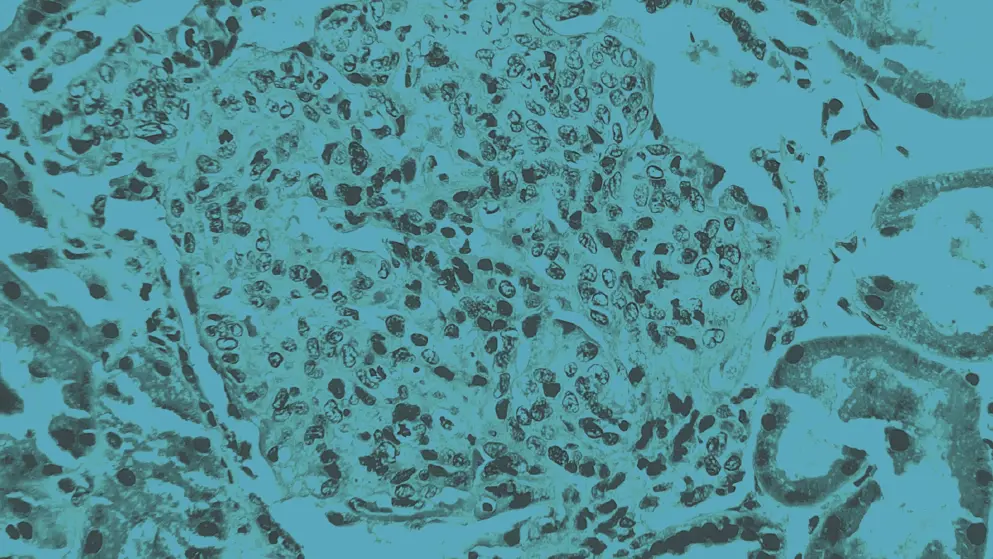

endocapillary hypercellularity in lupus nephritis, cellular image, blue overlay